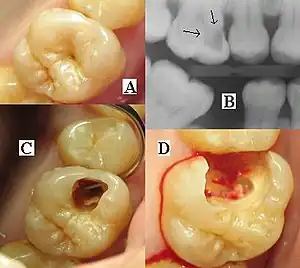

It is possible for both tooth decay and periodontal disease to be missed during a clinical exam, and radiographic evaluation of the dental and periodontal tissues is a critical segment of the comprehensive oral examination. The photographic montage at right depicts a situation in which extensive decay had been overlooked by a number of dentists prior to radiographic evaluation.